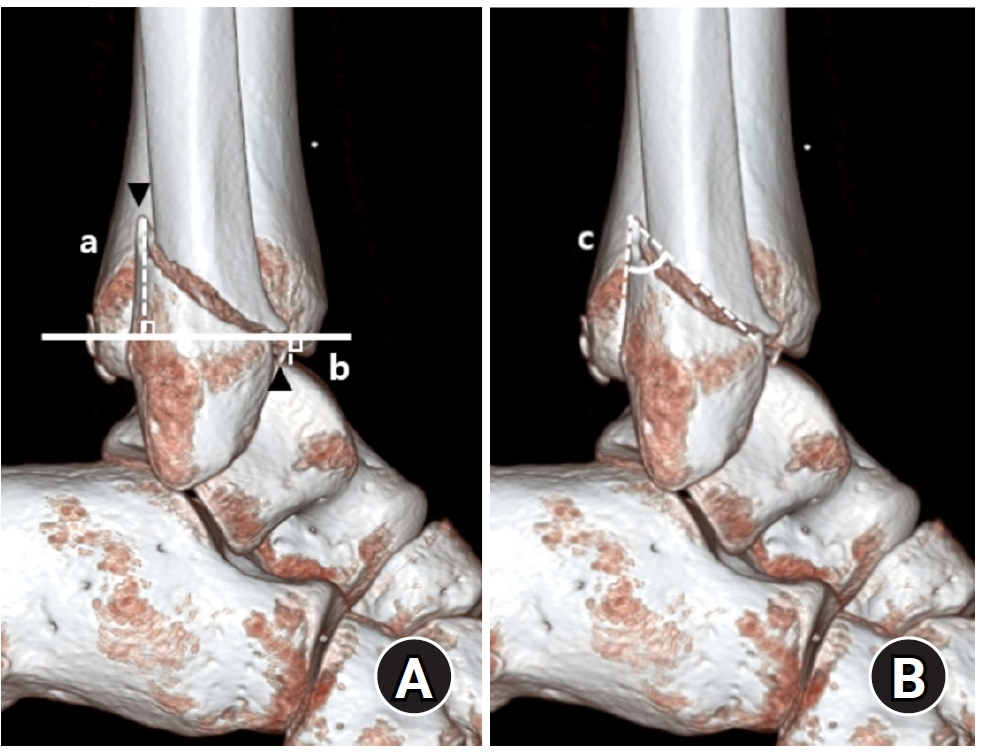

Regarding posterior malleolar fracture morphology, Haraguchi type III (small shell fragment) was more common in the <4.5 cm group, while type II (medial extension) predominated in the ≥4.5 cm group (P<0.001) (Table 2, Fig. 5). Similarly, the Bartonicek classification showed that type 1 (extra-incisural fragment with intact fibular notch) and type 2 (small posterolateral fragment extending into the fibular notch) were more frequent in the <4.5 cm group, whereas type 3 (posteromedial two-part fragment involving the medial malleolus) and type 4 (large posterolateral triangular fragment involving more than one-third of the notch) were predominant in the ≥4.5 cm group (P<0.001).

Fig. 3.

Bartonicek classification of posterior malleolar fractures. (A) Type 1: extraincisural fragment with an intact fibular notch. (B) Type 2: posterolateral fragment extending into the fibular notch. (C) Type 3: posteromedial two-part fragment involving the medial malleolus. (D) Type 4: large posterolateral triangular fragment.

Fig. 3. Bartonicek classification of posterior malleolar fractures. (A) Type 1: extraincisural fragment with an intact fibular notch. (B) Type 2: posterolateral fragment extending into the fibular notch. (C) Type 3: posteromedial two-part fragment involving the medial malleolus. (D) Type 4: large posterolateral triangular fragment.